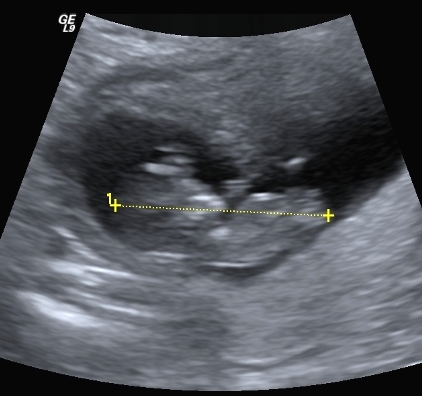

I finally managed to get hold of my u/s disc and have selected a few of the pics I think could have a nub in them (I'm still pretty hopeless at working out nubs).

There is only 1 pic from my 19 week scan that even comes remotely close to the bottom region and I'm pretty sure it is not a potty shot, just of legs from above I think??? (second last pic...biggest one)...I'm a little p'd off with the tech as I asked him to get a pic for me and he obviously didn't.

I have included quite a few from my early scan but bub was 11w4d so I understand prob slightly early still.